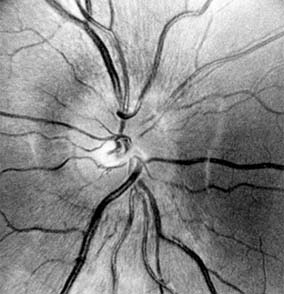

Figure 14-9

Figure 14-9: Mild papilledema. The disk margins are blurred superiorly and inferiorly by the thickened layer of nerve fibers entering the disk.